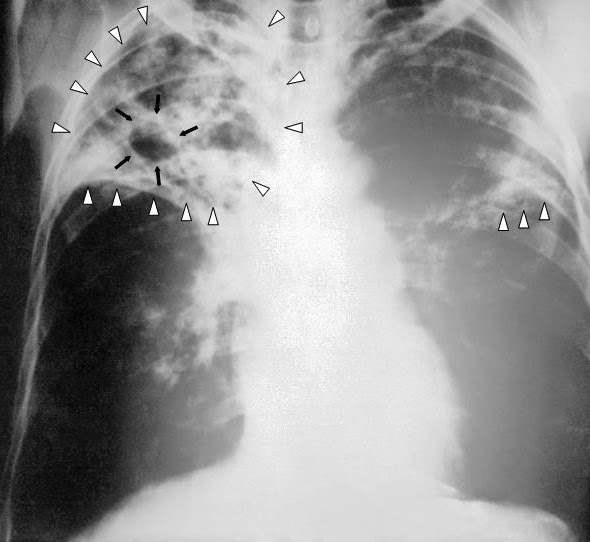

From www.ijidonline.com

Pulmonary cryptococcosis misdiagnosed as smearnegative pulmonary Is Tb Deadly If Untreated tb disease is one of the world's leading infectious disease killers. tuberculosis (tb) is a serious illness that mainly affects the lungs. Cdc estimates up to 13 million people in the united states live with inactive. However, the majority of people who undergo treatment have a. It can be fatal if not treated. tuberculosis (tb) can be. Is Tb Deadly If Untreated.